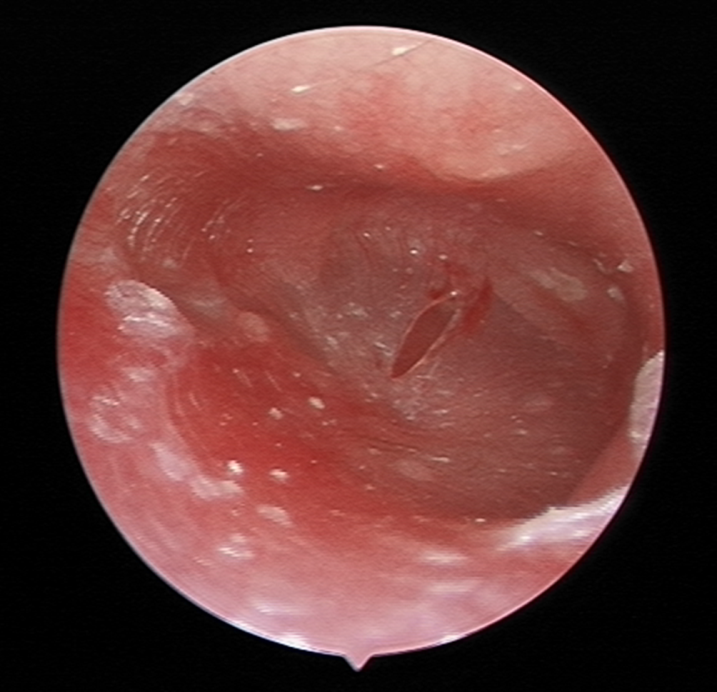

根据病史和临床表现以及辅助检查,分泌性中耳炎就比较容易诊断了,接下来就是治疗了。清除中耳积液,改善中耳通气引流及病因治疗为本病的治疗原则。90%以上的分泌性中耳炎保守治疗都能治愈,若经过正规的保守治疗3月以上无效者,可以行手术治疗,可以做鼓膜穿刺、鼓膜切开、鼓室置管术等。

图片

5鼓膜切开术,在鼓膜的紧张部做切口,切开鼓膜,排出积液

6 鼓膜置管术,先行鼓膜切开,在切口处植入通气管,改善鼓室通气。